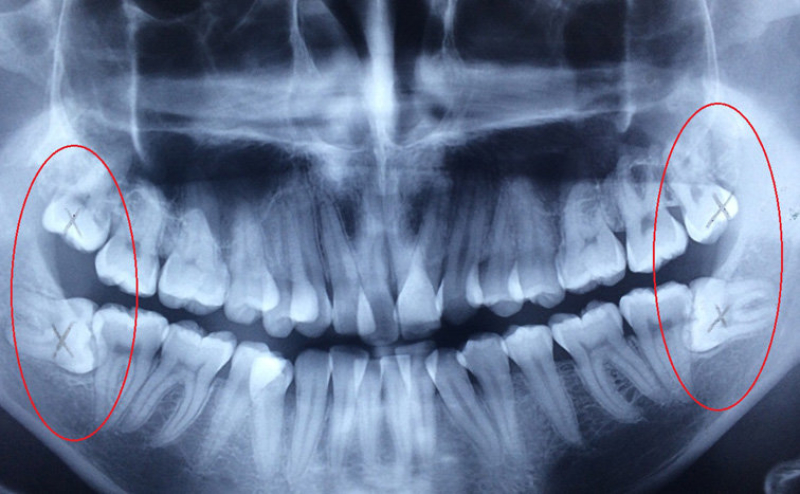

Formado por: boca, faringe, esófago, estómago, intestino delgado, intestino grueso, recto y ano. Su pared está compuesta de 3 capas: Una capa muscular longitudinal. Una capa muscular circular. Una capa interna de tejido epitelial o mucosa, con glándulas que producen mucus y jugos digestivos. Las capas musculares le dan elasticidad y movilidad (peristalsis). LA BOCA Orificio de entrada al digestivo. Cerrada por los labios. En su interior está la lengua, órgano muscular que ayuda a la masticación, deglución y percepción de sabores. La boca se comunica con la faringe o garganta, común a digestivo y respiratorio. DIENTES Los dientes son las partes más duras del cuerpo humano. Se encuentran alojados en cavidades de la mandíbula llamadas alveolos y unidos a las encías. Un diente tiene las siguientes partes: Existen cuatro tipos de dientes: Incisivos: (paletas). Corona plana y afilada. Sirven para cortar los alimentos. Caninos: con corona puntiaguda. Para desgarrar. Premolares: de corona ancha y aplanada. Para aplastar y triturar Molares: de igual forma y función que los premolares, pero mayores y con 3 raíces. Los humanos tienen dos denticiones. La primera aparece a los 6 meses y dura hasta los 6 años. Consta de 20 dientes (todos menos los molares). Es la llamada dentición de leche. La 2ª aparece a partir de los 6 años, sustituyendo a la anterior y añadiendo los molares, con lo que consta de 32 dientes. Es la dentición definitiva. FARINGE Garganta. Cavidad común al digestivo y al respiratorio. ESÓFAGO Tubo de 25 cm. Conecta la boca y el estómago, atravesando el diafragma. Se halla entre la tráquea y la columna vertebral. ESTÓMAGO Órgano en forma de saco. Capacidad de litro y medio. Tiene un orifico de entrada (cardias), comunicado con el esófago y controlado por un esfínter (músculo circular) y otro de salida (píloro), que lo comunica con el intestino delgado gracias a otro esfínter. La pared interna tiene una mucosa protectora y glándulas que fabrican el jugo gástrico. El estómago almacena el alimento y lo digiere en parte, controlando su paso al intestino. INTESTINO DELGADO Tubo largo y delgado, de unos 5 metros, por lo que se halla enrollado en el abdomen. Se divide en tres partes: Duodeno: primer tramo. Unos 25 cm. A él vierten los conductos biliares y pancreáticos. Yeyuno: parte media. En él se da principalmente la absorción. Íleon: porción final, y más larga, del intestino, donde se acaban de absorber los nutrientes. Desemboca en el intestino grueso por la válvula ileocecal. La pared del intestino delgado está muy plegada para aumentar su superficie de absorción. Además, estos pliegues presentan otros menores con forma de dedo llamados vellosidades, cuyas células tienen repliegues de la membrana denominados microvellosidades. De esta forma se consigue una superficie total de varios m 2 . INTESTINO GRUESO Tubo más grueso y corto que el intestino delgado. Mide 1,5 m y unos 10 cm de grosor. Se divide en: Ciego: primera porción, con forma de fondo de saco y con una prolongación de unos 7 cm llamada apéndice vermiforme. Colon: parte más larga, con forma de ‘U’ invertida. presenta una porción ascendente, una transversa y una descendente. Recto: última porción. Acumula las heces antes de su salida al exterior. ANO Orificio de salida del digestivo, situado al final del recto, y controlado por el esfínter anal. A través de él se expulsan las heces al exterior.